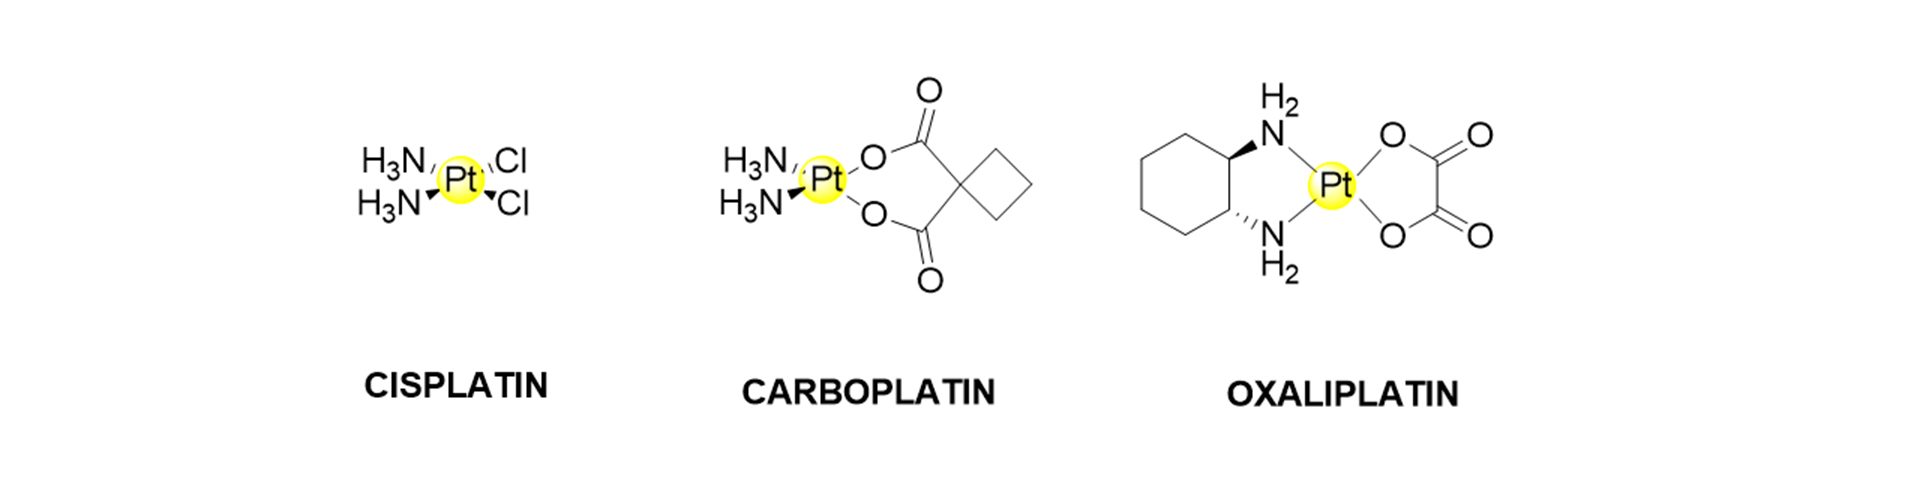

Cisplatin is the most critical chemotherapeutic drug used worldwide to treat different cancers, including osteosarcoma. The structure of cisplatin and its common derivatives are shown in Fig. 1. The main drawbacks associated with its use are the lack of selectivity for cancer cells and its high toxicity. Cisplatin and other approved platinum chemotherapeutic drugs (i.e. carboplatin and oxaliplatin) are nephro and ototoxic. In many cases, tumours develop resistance mechanisms after several chemotherapeutic cycles, and the therapy must be halted.

One strategy under investigation is the use of specific vectors that could deliver platinum-based drugs to the targeted tissue, such as carbohydrates whose receptors are overexpressed in cancer cell membranes. Within the Nano4TarMed project, Montagner’s group is developing new platinum-based drugs that could be anchored to the nanoplatform developed by the Ranc lab at Palacký University to enhance tumour selectivity and diminish the toxic side effects.